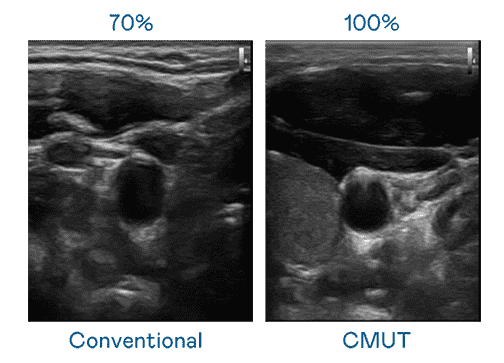

CMUT 技术是一种用电容式微机电元件来产生超音波讯号的技术。。与传统 PZT 压电式技术相比,,,CMUT 频宽增加 30%,,,,更宽频的超音波讯号让影像解析度大幅提升,,,是实现高影像品质医疗超音波扫描、、促进精准医疗发展的关键技术。。

超音波影像的解析度高低,,,,首先取决于探头能发出的讯号频宽。。。。壹号平台 CMUT 可提供高清晰的超音波讯号,,,,提供高频宽、、、、高灵敏度、、、、影像纹理细节更高的超音波影像,,,,协助医护人员缩短影像判读时间及利用精准的医疗影像进行诊断。。。